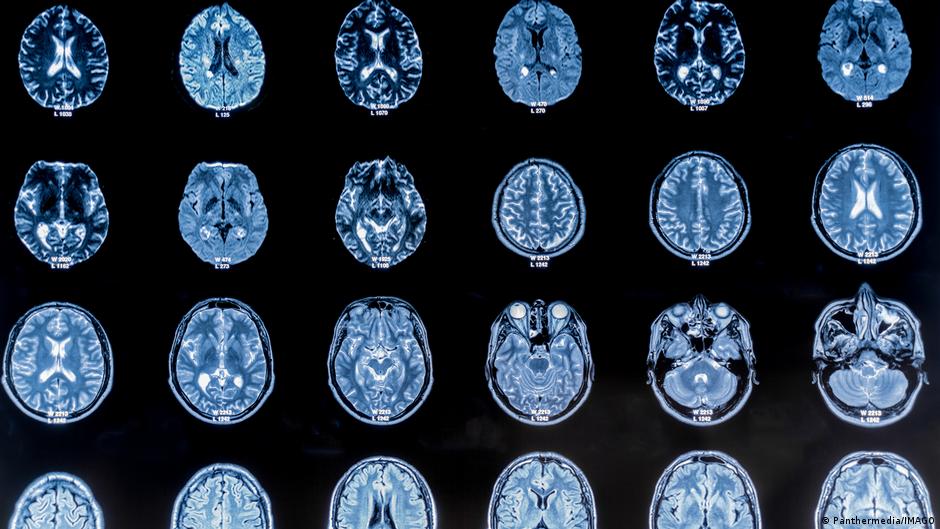

Istraživački tim sa Univerziteta Kembridž je analizirao 3.802 MRT snimka mozga i rekonstruisao obrasce neuronske povezanosti između rođenja i 90. godine. Podaci su otkrili iznenađujuće jasnu sliku: Strukturna organizacija mozga ne odvija se kontinuirano, već u pet glavnih faza od kojih je svaka obilježena značajnim prekretnicama – oko 9. 32. 66. i 83. godine.